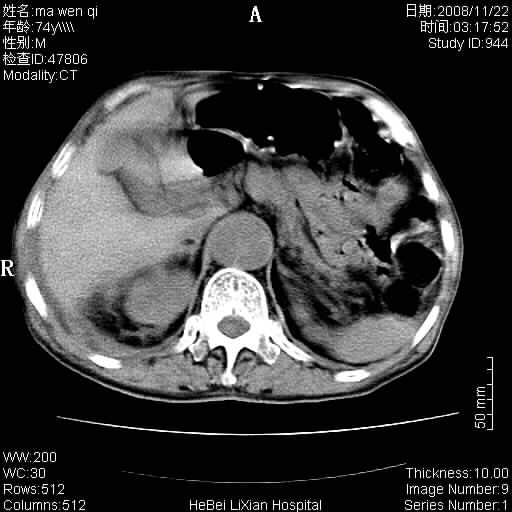

患者男 74岁.突然昏迷,休克6小时.血压70/30,头颅ct未见异常,既往体健.

补充病史,保留导尿10小时,尿袋内只有少许尿液,患者于住院后15小时后去世.

腹主动脉、双侧髂动脉夹层动脉瘤破裂出血进入腹腔。

1)考虑双侧髂动脉瘤并右侧动脉瘤破裂出血,右侧腹膜后及腹腔积血。2)双侧腹股沟疝。

1)考虑,腹主动脉、双侧髂动脉夹层动脉瘤破裂伴右侧腹膜后及腹腔积血。2)双侧腹股沟疝。

1)考虑胸、腹主动脉、双侧髂动脉瘤并右侧动脉瘤破裂出血,右侧腹膜后及腹腔积血。2)双侧腹股沟疝。